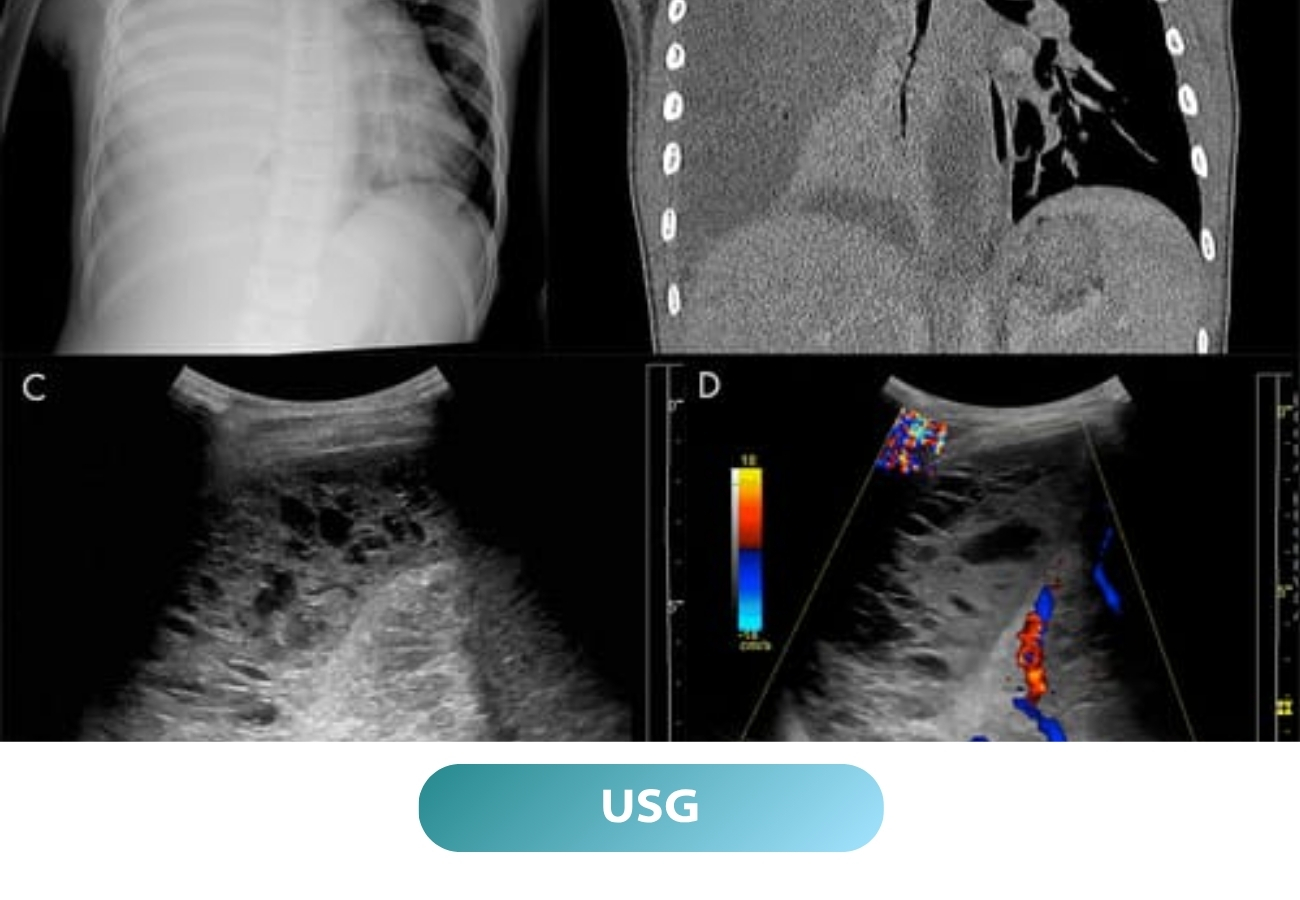

Quick tests like spirometry and chest X‑rays help us find problems early, so you get the right treatment fast.

Advanced tools like spirometry and chest X-rays to help diagnose lung problems quickly and accurately.